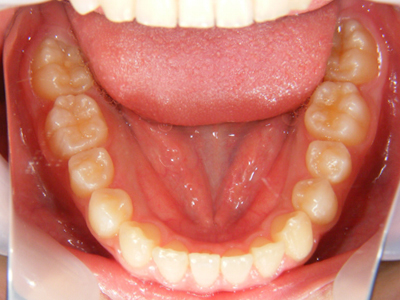

3. 術前下顎

下顎面観ではやはり右下1番の舌側転位、左下2,3番間の叢生が目立ちます。右下5番(第2小臼歯)が左側の同5番に遅れて萌出途中にあります。